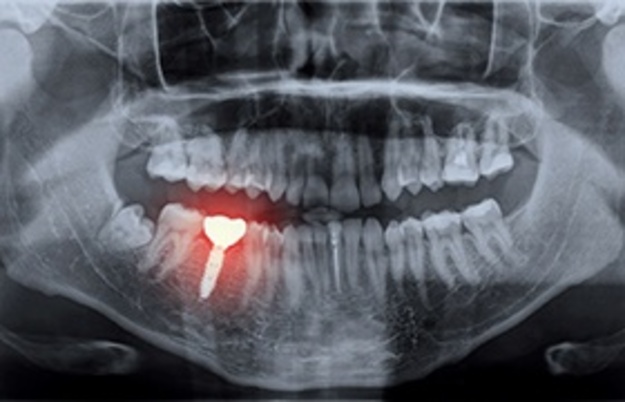

Failing Dental Implants? Here’s How to Save Your Smile and Avoid Disaster

Dental implants are often hailed as the ultimate solution for missing teeth, offering durability, function, and a natural look that can last decades. Yet, even these […]

How Dental Implants Save Teeth Affected by Bridge Failure at Dr. Thomas Dental Implant Clinic in Dubai

A Complete Guide for Dubai Residents and International Patients Dental bridges have long been used to replace missing teeth and restore smiles. However, even the best […]